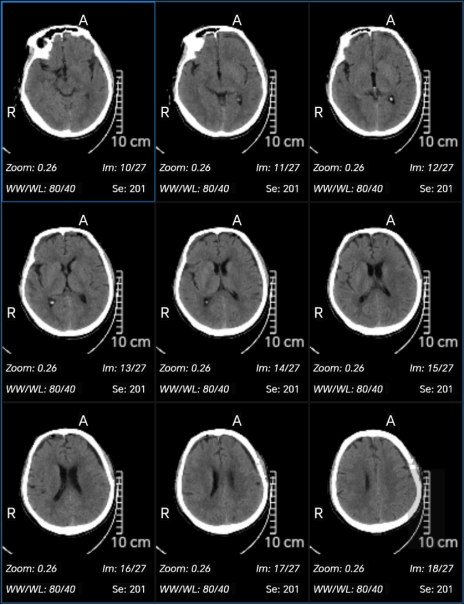

术后第1天CT

术后第4天CT

随访CT